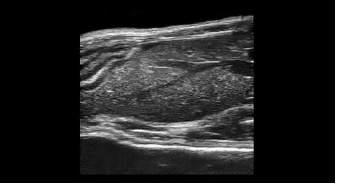

動物種別アプリケーション画像例

ラット |

| ▲肝臓の血管系 | ▲腎臓と副腎 |

| ▲腎臓の血管系(3Dカラー) | ▲脾臓 |